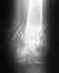

С большим трудом идет разработка контрактуры коленного сустава. После получения травмы прошло 5 месяцев. Ногу начал разрабатывать полтора месяца назад. Процесс идет с трудом. У меня был перелом левого бедра после ДТП. Была проведена операция. Бедро скрепили пластиной с винтами. Кость уже срослась. Разрешили наступать. Но эта контрактура коленного сустава мешает мне жить. Можно ли разработать ее на 100% после прошествия 5 месяцев? Сейчас нога при максимальном давлении при разработке сгибается до 95 градусов. В повседневной жизни нога сгибается только на 75 градусов.Уважаемые доктора, подскажите пожалуйста может быть какие-нибудь еще упражнения и сколько раз в день их надо выполнять. Подскажите медицинские учереждения, где разрабатываю контрактуры коленного сустава.Мне кажется, что рубец на квадрицепсе с левой стороны после операции не дает мне разработать ногу. Вдоль рубца мышца натянута неимоверно при разработке. В моем городе нет нормальной механотерапии. Хожу только к массажисту, которая также сгибает мою ногу после массажа.Благодарю!